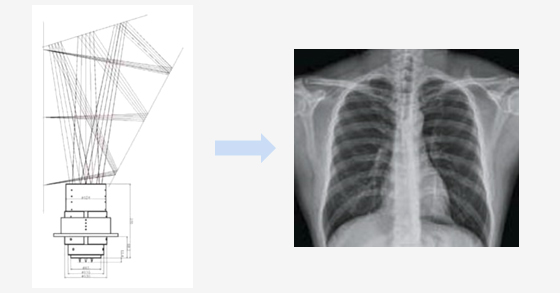

The medical CDR lens is a lens for X-ray photography, and can verify even observation after photographing in a very short time, as compared to the manner of photographing with ordinary films.

- Purpose : For medical (X-ray photographing)

- Lens Shape